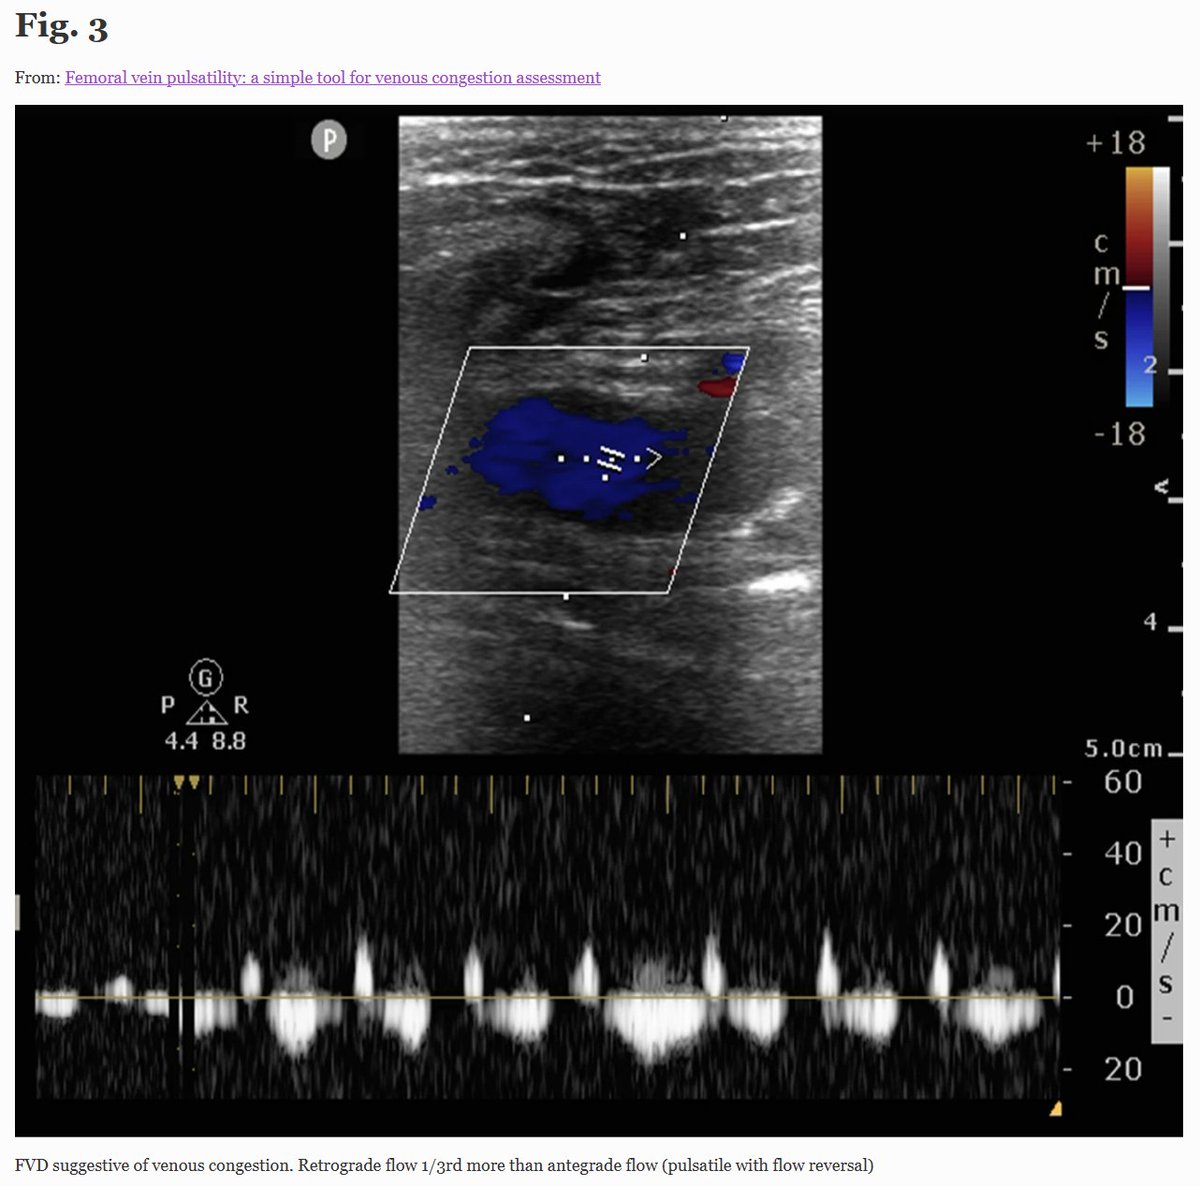

Is this new slick technique the new kid on the block of venous assessment? Promising and fast, so why not? https://t.co/czzx486euV